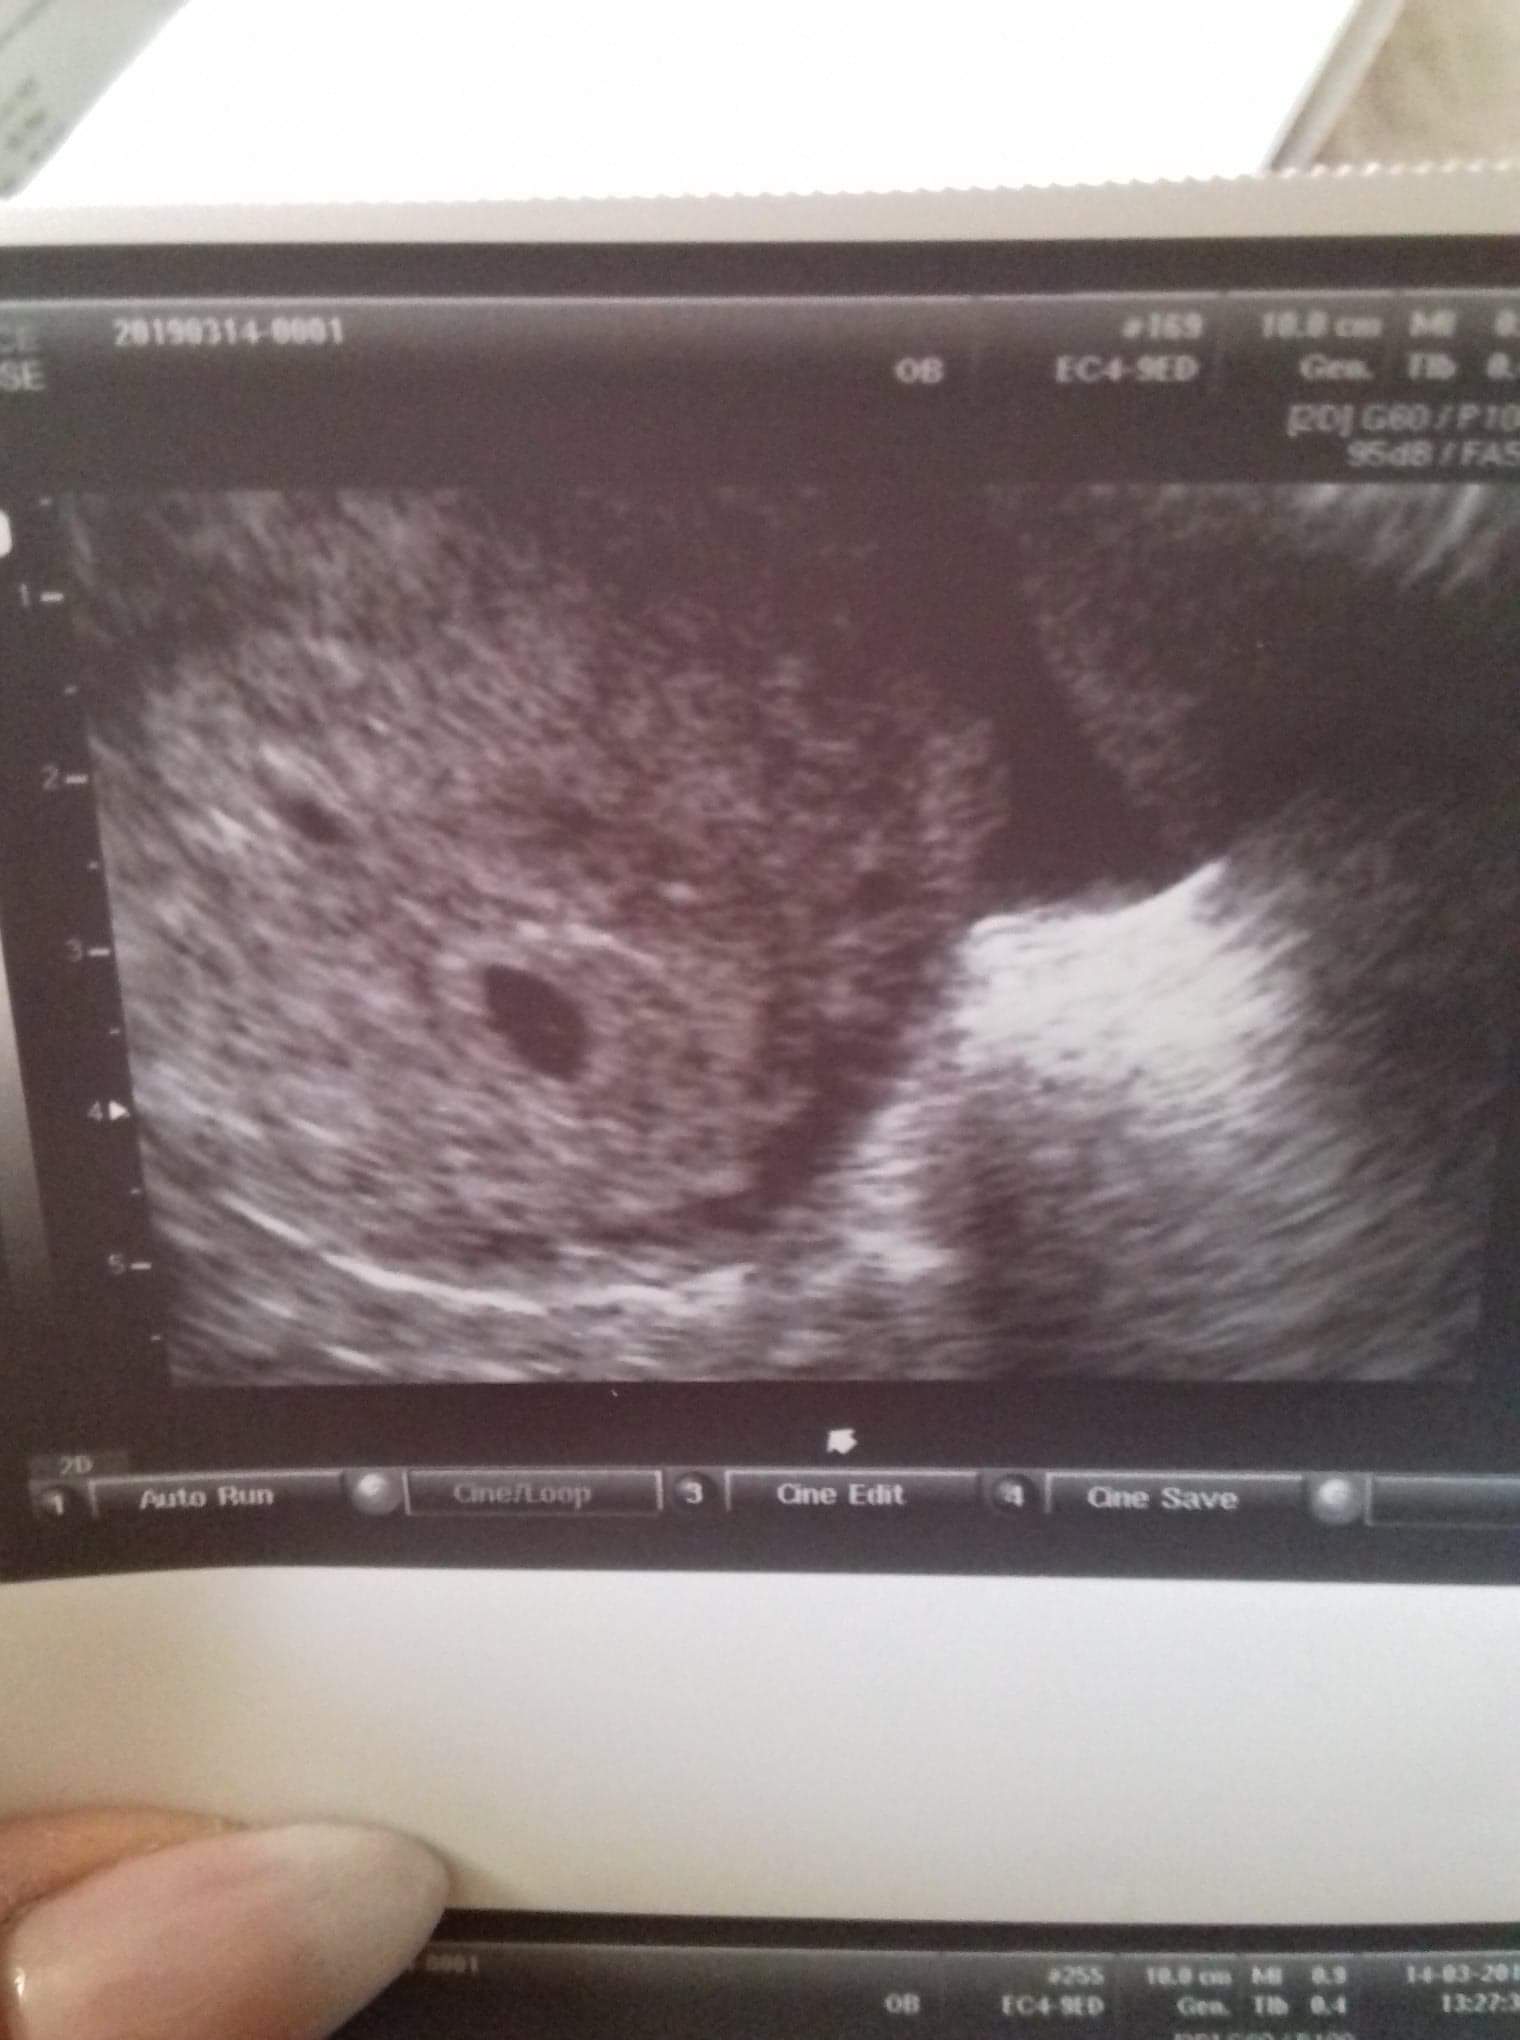

Czy to ciąża bliźniacza ?

Witajcie drogie mamusie. Czy to mozliwe że na zdjęciu widać 2 pęcherzyki ciążowe? Na zdjeciu tydzien 4-5 (nieregularne miesiaczki stąd ta rozbieżność). Pani ginekolog nie poinformowała mnie ze jest to ciąża bliźniacza, z resztą nie wpadło mi do głowy zeby zapytać czy to ciaza mnoga. Na badaniu usg nie widzialam drugiego pęcherzyka. Dopiero gdy pokazalam zdjecie usg mojej mamie stwierdziła ze widzi nie jeden a dwa pecherzyki. Są one różnej wielkości dlatego też zastanawiam się czy to możliwe ze to ciąża bliźniacza. Czy któraś z was byla w podobnej sytuacji? Byla w ciąży mnogiej, a wielkość pęcherzyków się różniła? Jeśli macie zdjęcia usg z wczesnej ciąży ze swoimi maluszkami chętnie popatrzę Pozdrawiam

Hej u mnie stwierdzili ciąże bliźniaczą dopiero w 6t4d, jak byłam w 4t to było widać dokładnie to co u Ciebie i nikt mi wtedy o bliźniakach nie powiedział. Po ostatnim USG wciąż kazali do tego podchodzić spokojnie. Zobaczymy co pokaże następne badanie.

Ja po latach dołączam do pytania i załączam zdjęcie. Co myślicie o tym . Lekarza spytałam o bliźniaki ale powiedział że jeden dzidzius, zaśmiał się i powiedział że kto wie co się rozwinie jeszcze bo wszystko możliwe .